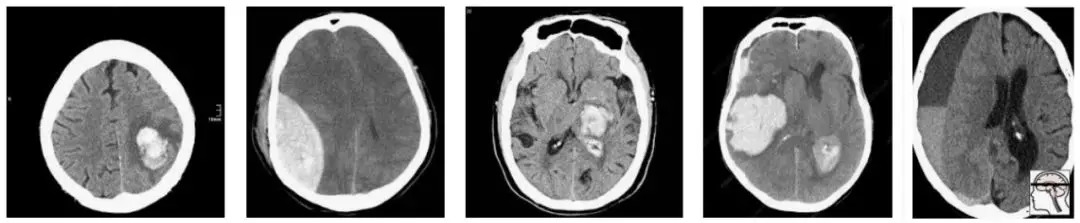

最近,一个新的大型CT脑扫描数据集被发布,其目的是训练模型以检测颅内出血。

那么我们如何处理多重假设检验呢?这一切都归结于问题的原因,即数据。Epi101告诉我们,任何测试集都是目标总体的一个有偏差的版本。在这种情况下,目标人群是“所有CT头部成像的患者,有或无颅内出血”。让我们来看看这种偏见是如何产生的,举一个小的数据集示例:

在这一人群中,我们有相当合理的“临床”病例组合。3例脑内出血(可能与高血压或中风有关),2例创伤性出血。

现在让我们对这个群体进行抽样,以构建我们的测试集:

随机地,我们抽样得到的大部分是轴外出血。在这项测试中表现良好的模型不一定能在真实的患者身上发挥同样的效果。事实上,你可能期望一个擅长轴外出血而牺牲脑内出血的模型获胜。